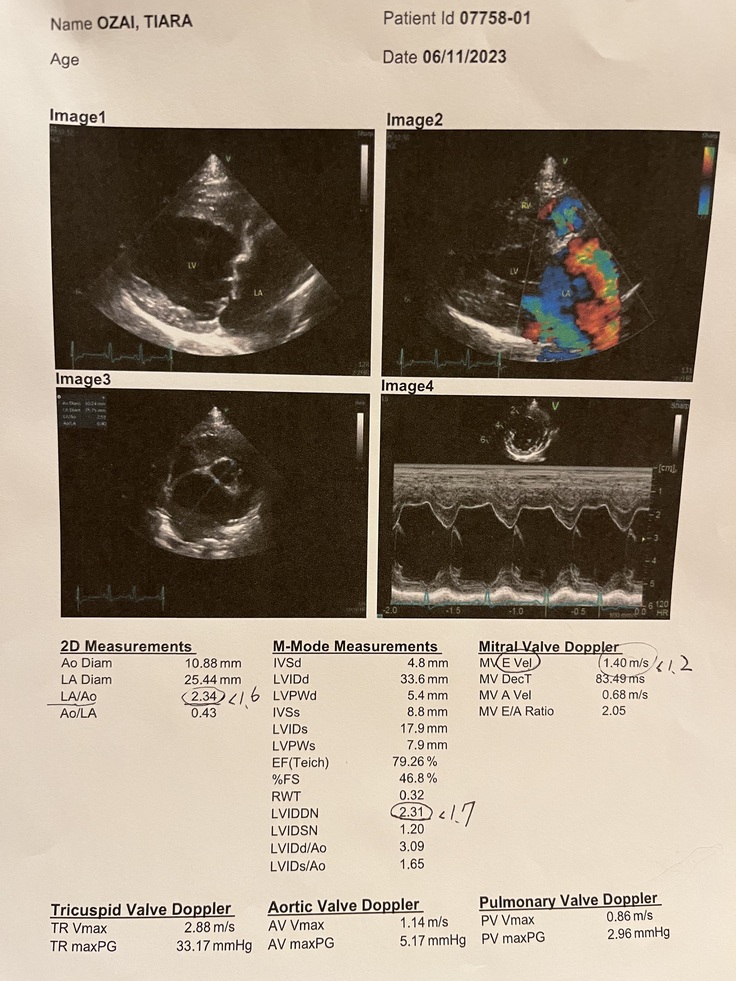

初めまして、ティアラの飼い主の小材です。

▼クラウドファンディングを作成した経緯

愛犬ティアラが

『僧帽弁閉鎖不全症ステージC

心原生肺水腫』

になってしまった為。

▼病気発症からの経過

2022.2

動物病院でワクチン接種の際に

聴診で心雑音を発見。

心肥大も見られた為、投薬開始。

病名『僧帽弁閉鎖不全症ステージB1』

2023.9月26日

半年検診、心雑音、心肥大は今まで通り

エコー、超音波、レントゲン、血液検査

半年前と大きく変わらず増薬もなし。

2023.10.09

自宅で急な転倒

低血糖のような症状で口周りや歯茎が真っ白

手足硬直、痙攣発作

今回の発作が心臓病からくる物なのかを検査

レントゲンを撮りその結果

『かなり心肥大が進行しており

肺に水が溜まり

肺水腫を起こしている。』

との事。

危険な状態にあった為

利尿剤を入れ排泄させ、一時的に回復。

酸素室での管理を余儀なくされる。

2023.10.12

かかりつけの病院から

循環器専門の病院をご紹介頂き

群馬県内の動物医療センターさんへ

循環器専門の獣医さんとお話しをし

再度、全身の検査

心原生肺水腫

余命、6ヶ月〜9ヶ月です。』

との診断。

2023.11.6

手術を決心し

お願いする循環器専門病院にて

術前検査。

心肥大や肺の状態などを診て頂き

総合的な判断で

今が手術を受けるタイミングで良さそう

との事でした。

さらに脾臓にリンパ腫も見つかった為

2023.11.15に脾臓の細胞診の検査をし

リンパ腫の疑いとの判断になり

そちらは僧帽弁閉鎖不全症の手術後に

経過を診て、摘出手術になりました。

※こちらが脾臓の腫瘍のレントゲンです。

▶︎4. 掲載している資料について

ページ上に掲載している診断書や

診療明細書などの資料は全て動物病院から

掲載の許諾を得ております。